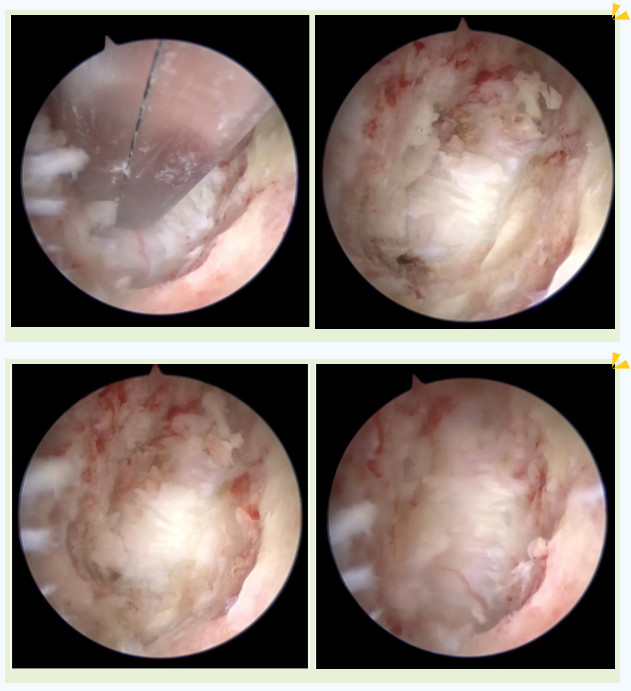

手术图片

吴阿婆手术时的内镜下图片

突破后纵韧带后顺利到达颈髓